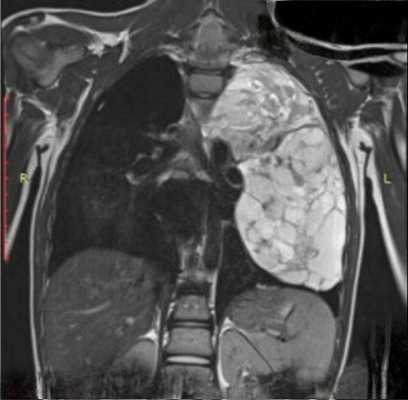

Материалы РОНЦ подтверждают известные сведения о локализации и преимущественно злокачественном характере опухолей осредостения. Соотношение злокачественных и доброкачественных новообразований составило 3:1. Тимомы, лимфомы, внегонадные герминогенные опухоли (ВГО), мезенхимомы локализовались в переднем средостении, нейрогенные опухоли - в заднем; несоответствие локализации и структуры новообразования отмечено у 15% больных нейрогенными опухолями - в тех случаях, когда новообразования локализовалась в переднем средостении. Определение исходной локализации процесса было затруднено при «гигантских» опухолях, когда (в 10-20% случаев) наблюдались поражения как переднего, так и заднего средостения с распространением процесса на б?льшую часть гемиторакса.

Длительность клинических проявлений составляла от нескольких месяцев до 3 лет. При небольших опухолях, не связанных с прилежащими анатомическими образованиями не отмечалось клинических проявлений (до 30-40% случаев). В остальных наблюдениях регистрировались проявления, обусловленные наличием опухоли - миастения (5%), осиплость (часто сопряженная с ВГО), медиастинальный компрессионный синдром (до 30-40% случаев, в особенности при злокачественных процессах); а также различные неспецифические симптомы (повышение температуры тела, кашель, боли и чувство сдавления за грудиной, др.). Рентгенологическое исследование, безусловно, позволяло определять локализацию и размеры опухоли. Для уточнения топографии новообразований, выявления связей с прилежащими анатомическими образованиями применялись КТ и МРТ. Чувствительность. специфичность и точность * этих методов соответствовали 90-80%, достигая 97-98% значимости оценки - как например, МРТ в диагностике распространенности тимом. Повышение уровня опухолевых маркеров сыворотки крови (АФП и ХГЧ) наблюдалось при несеминомных герминогенных опухолях средостения. Морфологическое подтверждение диагноза, кроме пункционной биопсии (информативность, при лимфопролиферативных заболеваниях, соответствует 48%), достигалось хирургическими методами диагностики. При этом, вместо медиастиноскопии и парастернальной медиастинотомии (16 и 43 исследования 1990-х гг.) в 2000-х гг. стала применяться видеоторакоскопия (53 исследования).